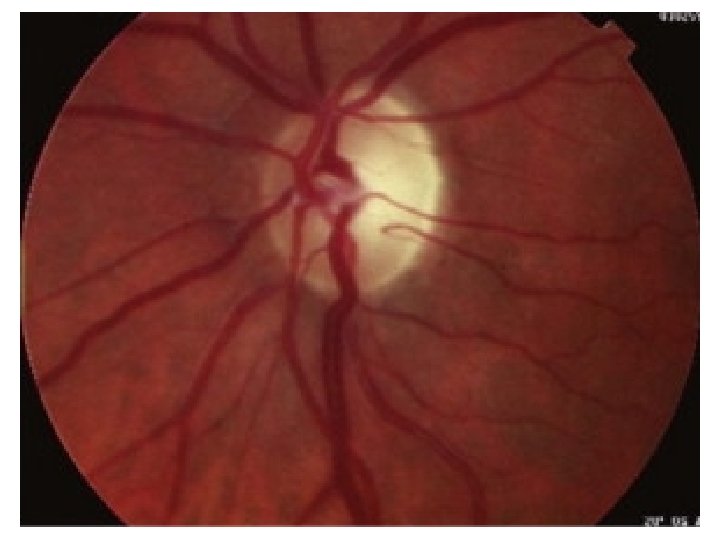

AION • Elderly patients (age >65) • Sudden and severe loss of vision in one eye initially • Systemic symptoms are headaches, scalp tendemess, malaise, jaw claudication • Vision 6/60 or worse RAPD • Extensive visual field loss • Pale swollen optic disc (anterior ischaemic optic neuropathy), rarely CRAO.

AION • • • Aim to prevent loss of the other eye! Urgent ESR (expect >60) Prednisolone l 00 mg stat Urgent referral Temporal artery biopsy will confirm the diagnosis